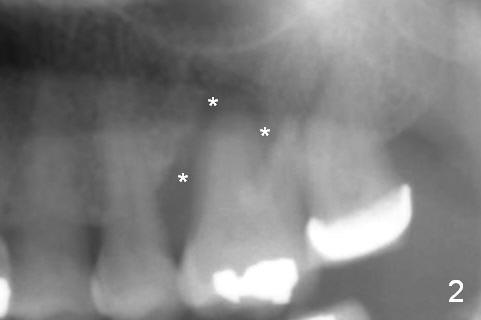

A 54-year-old woman has history of chronic periodontitis with bruxism. Bone loss at the tooth #14 starts at the mesial crest (Fig.1: 2008), extends to the mesial root (Fig.2, 2015) and the palatal one (Fig.3, 2016). The periodontal pockets are deep with mobility III. Since the defect is large with low bone density, Magic osteotomes are going to be used for CMC immediately after extraction (Clindamycin). If there is no history of sinusitis, a 11 mm long implant will be placed (Fig.4). Allograft (.5-1.5 mm) will be delivered with the large bone carrier for CMC (prior to implant placement) and the amalgam carriers for socket gap closure (before and after implant placement).